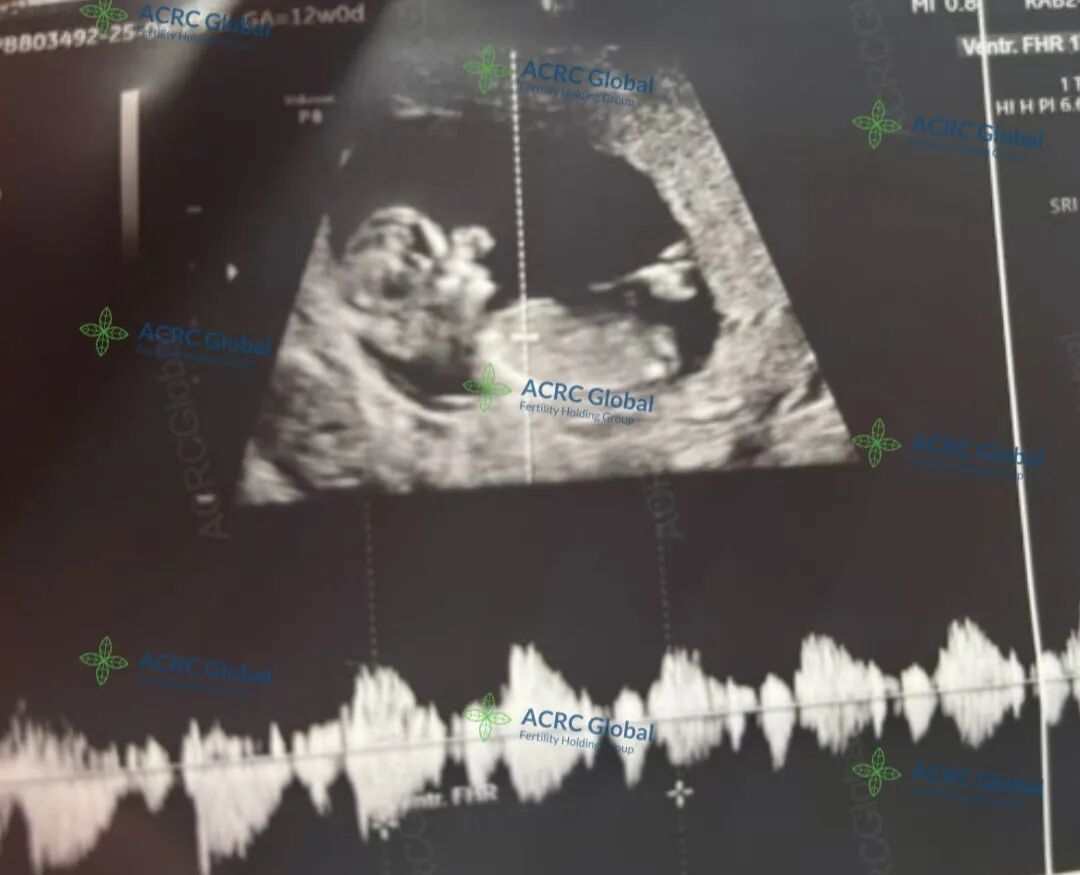

爱妈J的第二次孕期旅程正温柔而顺利地进行着,目前胎宝宝已满12周3天,胎心率高达172次/分,跳动着小小生命的蓬勃力量。这个阶段的宝宝已经初具人形,五官轮廓逐渐清晰,四肢也变得灵活,正在爱妈温暖的子宫中悄悄伸展、成长,每一刻都洋溢着勃勃生机。

这一次的宝宝,是准妈妈梦寐以求的小王子。在胚胎移植前,准父母特别选择了在美国应用广泛的PGT(胚胎植入前遗传学筛查)技术,对胚胎进行了全面的染色体筛查。这项技术不仅显著降低了遗传疾病的发生风险,也在法律允许范围内进行了性别筛选,实现了XY优选。于是这个被期待已久的男宝宝,如愿而至!我们也满心期待着,迎接他闪亮登场的那一天!